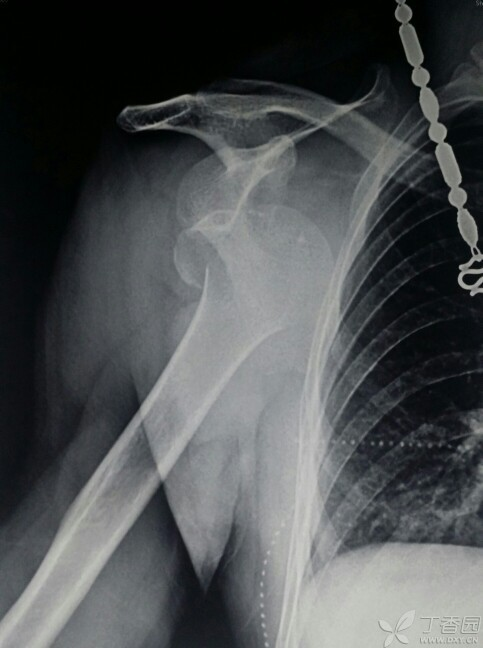

都这么简单吗?还真不一定,如果让你遇到了肩关节脱位合并隐匿性骨折就是一个巨大的坑了。看看下面的病例:

看片子似乎是一个简单的肩关节脱位并大结节撕脱骨折。

整复后拍片复查却成这个样子了……

其实这种往往都是合并了肱骨颈部隐匿性骨折。

临床上还真不罕见,只要遇到一例绝对让你头大如斗,因为骨折移位合并脱位处理起来极为麻烦,一般都预后欠佳。